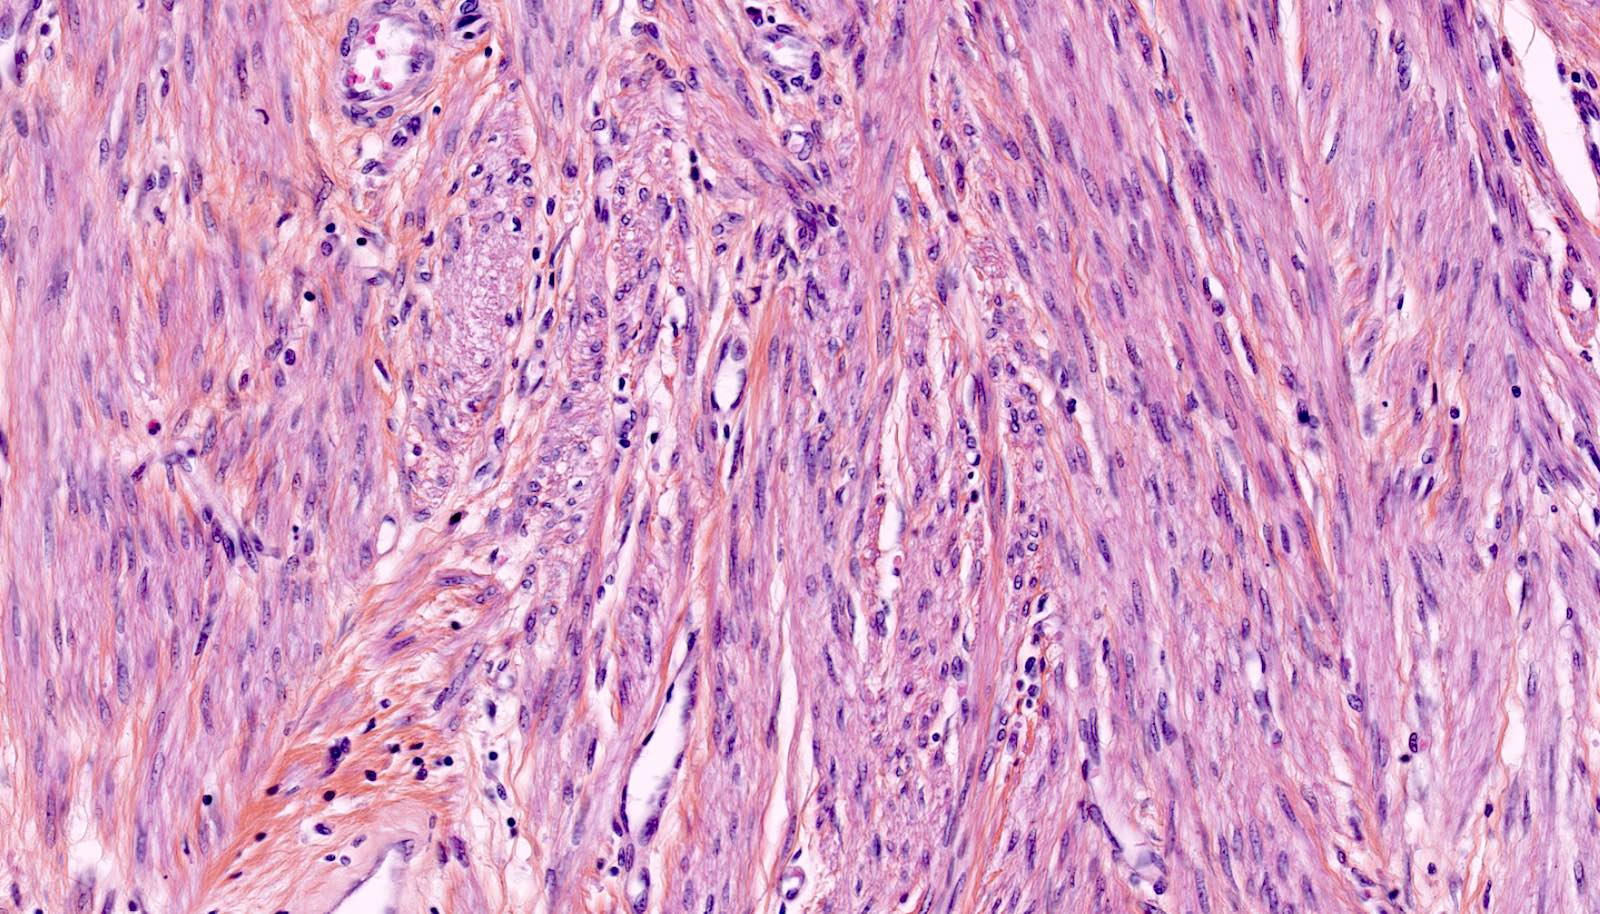

Microscopic (histologic) description

- Conventional / usual leiomyoma (spindle):

- Well defined borders

- Normocellular

- Intersecting fascicles of monotonous spindle cells with indistinct borders, eosinophilic cytoplasm, cigar shaped nuclei (with tapered ends) and small nucleoli

- Atypia: absent or mild

- Mitoses: rare (in general < 5/10 high power fields)

- Blood vessels with thick walls

- With or without infarct type necrosis, hyalinization, calcification, cystic change

Microscopic (histologic) images

Contributed by Sabrina Croce, M.D., Ph.D., Kristina Doytcheva, M.D., Jennifer A. Bennett, M.D. (Case #508) and @Andrew_Fltv on Twitter